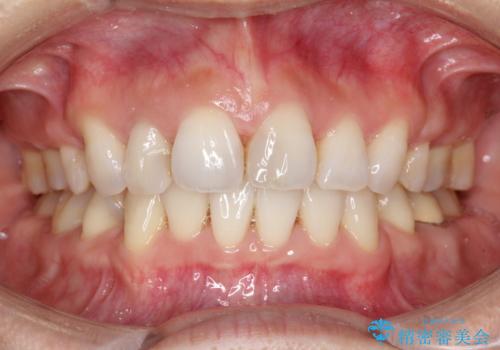

ワイヤーによる抜歯矯正でガタガタと深いかみ合わせの改善

上下の前歯の叢生とかみ合わせが深い過蓋咬合という状態でした。

かみ合わせの深さを改善するのに時間がかかり、予定よりも治療期間が長期化しましたが、整った歯並びへ改善することができました。